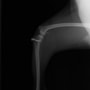

■ 症例22 ポメラニアン 1歳5か月 去勢雄

左後肢の挙上を主訴に来院した。整形学的検査、レントゲン検査より左右の膝蓋骨脱臼(左GradeⅡ〜Ⅲ、右Grade Ⅱ)を認めた。また、脛骨の前方引き出し試験の際に、引き出し兆候は認められないものの、疼痛が認められたため、前十字靭帯の損傷が疑われた。術中における、目視および関節内の操作によって、前十字靭帯の損傷や過伸展といった異常が認められなかったため、膝蓋骨脱臼の整復のみ実施した。手術手技は縫工筋及び内側広筋の解放、脛骨粗面の外側転位、滑車ブロック形造溝術、内外側関節包の縫縮を実施した。本症例は跛行もなく経過良好である。しかし、頸骨高平部の角度(TPA)が 右26.2°、左24.9°であり、解剖学的に前十字靭帯損傷のリスクが高いことから今後の経過に注意が必要である。